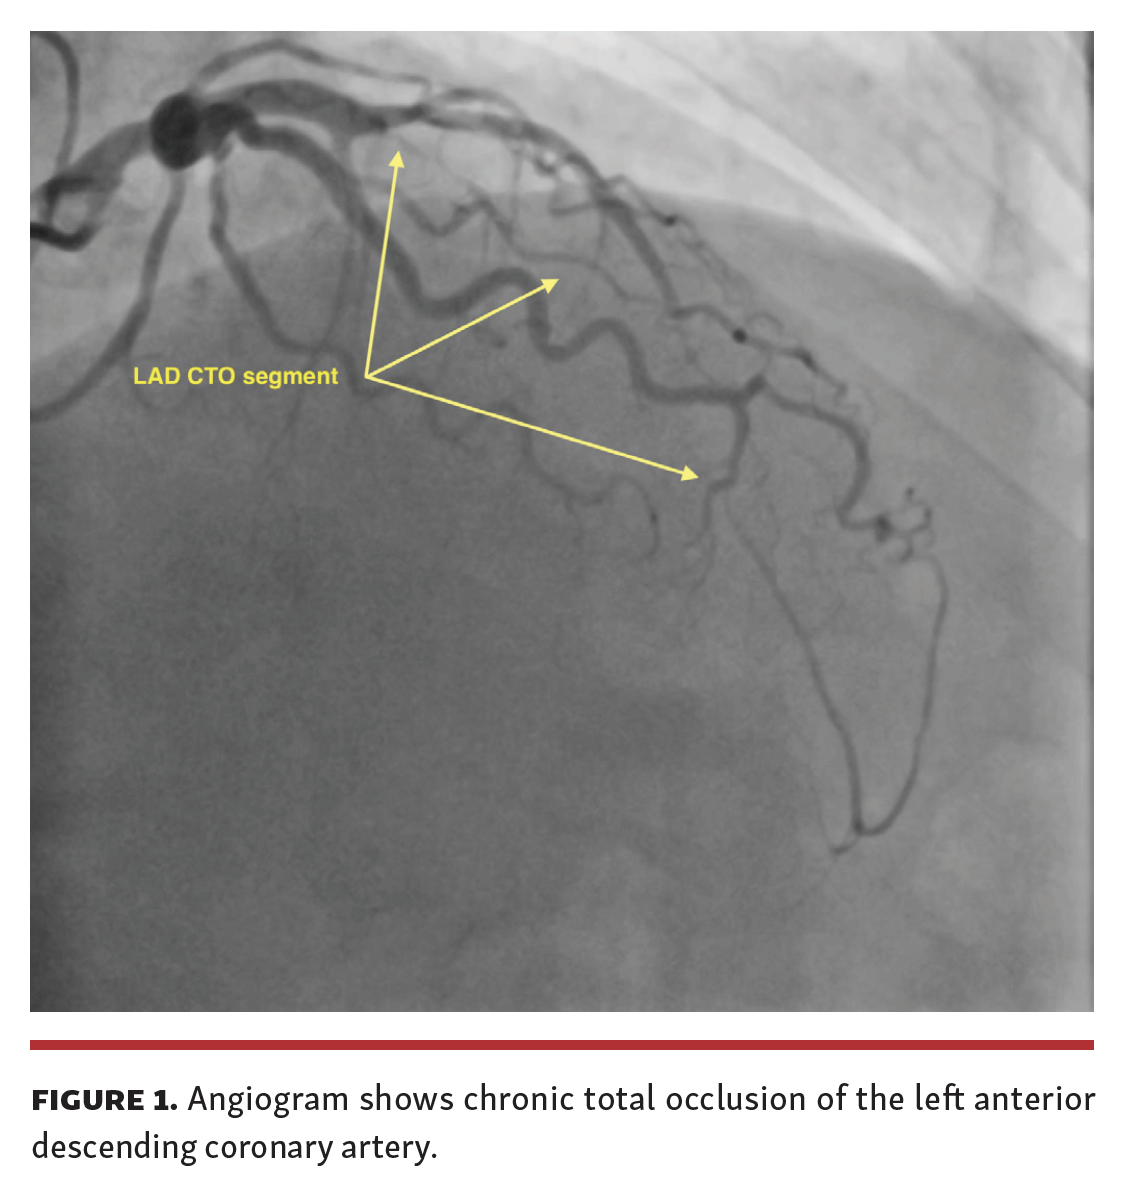

A 48-year-old male patient with a known diagnosis of hypertension presented after 6 months of chest pain (Canadian Cardiovascular Society II-III). Coronary angiography (CAG) showed a chronic total occlusion (CTO) of the left anterior descending (LAD) coronary artery from the mid-region (Figure 1 and Video Series). Percutaneous coronary intervention (PCI) was planned upon detection of viable tissue with myocardial perfusion scintigraphy. The distal portion of the CTO lesion was passed with microcatheter support and a hydrophilic wire. Distal flow could not be achieved despite successive predilations with small-diameter balloons (Figure 2). It was decided to implement an investment procedure to facilitate the next PCI process. Control angiogram 6 months later showed Thrombolysis in Myocardial Infarction (TIMI) 3 flow in the distal lumen of the LAD and there was no residual stenosis (Figure 3).